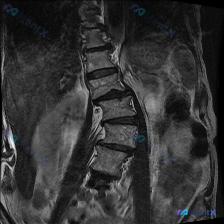

整理到一张腰椎MRI的冠状位T1WI图像,先不说结论,大家第一眼会怎么看?

目前能看到的影像表现:

- 腰椎明显向右侧凸,有椎体旋转和倾斜

- 两侧椎间隙高度不均匀,部分变窄

- 多个椎间盘信号降低

- 椎体骨髓信号基本是弥漫中等偏高,没看到明确的局灶骨质破坏或大肿块

- 两侧腰大肌形态不对称

这份资料里有几个点比较值得讨论,尤其是别被最明显的「侧弯」带偏了思路。